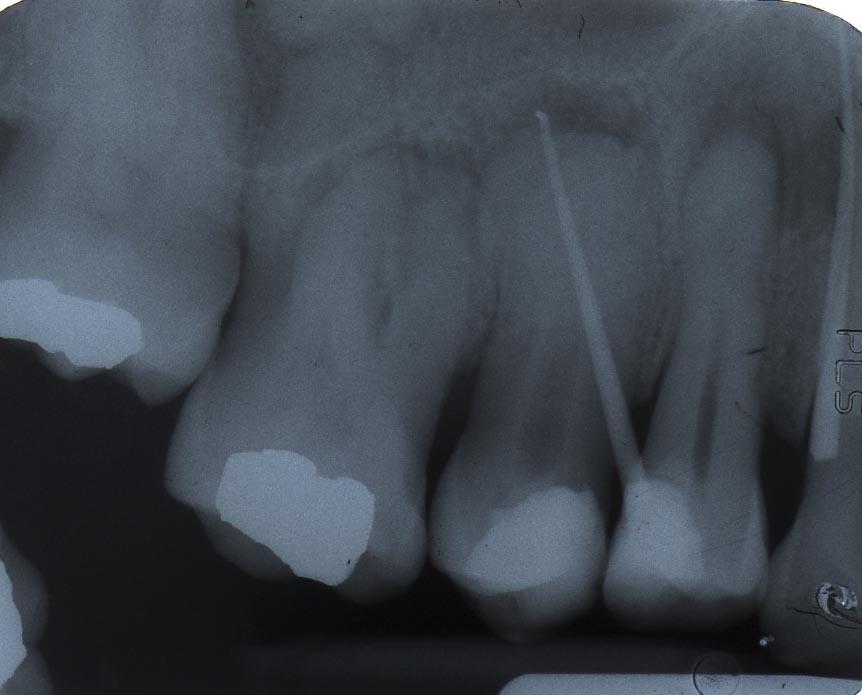

The process begins with the patient receiving local anesthesia to ensure their comfort throughout the treatment. Then, utilizing state-of-the-art techniques and advanced equipment such as digital imaging and operating microscopes, the endodontist meticulously removes the infected or damaged pulp from the tooth’s root canals while ensuring minimal discomfort for the patient.

These specialists alsouse their expertise to address complex cases involving intricate root canal anatomy or failed previous root canal treatments. Their precision and attention to detail enable them to effectively clean and disinfect the canals before filling them with biocompatible materials like gutta-percha.